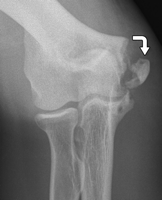

Injuries in young throwing athletes are on the rise, and elbow and shoulder injuries are the most common. Thousands of children are seen each year complaining of elbow or shoulder pain. Damage or tearing to the ulnar collateral ligament (UCL) or growth plates in the elbow and shoulder are the most common injuries suffered and are often caused by pitchers throwing too much.  When any of these structures become damaged it can take weeks to months to rehabilitate (and, worst case scenario, surgery).  When athletes are forced out of any sport due to injury, it can jeopardize their chances of attending showcases and it can inhibit their overall performance if they are trying to play through the injury.